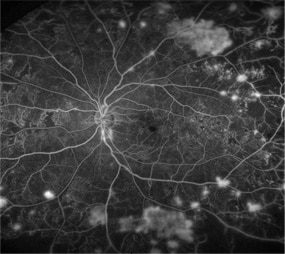

・蛍光眼底造影

蛍光色素の入った造影剤を腕の静脈から注射して、眼底カメラで眼底の血管を観察します。

血管の形や位置、血管からの血液中の水分のもれ具合などがわかります。

<糖尿病網膜症、糖尿病黄斑浮腫>

糖尿病網膜症、糖尿病黄斑浮腫

※検査の際には造影剤を注射するため、まれに吐き気や嘔吐、アレルギー反応などの副作用が起きることがあります。

検査中に何か異常を感じたら、速やかに医師に伝えてください。